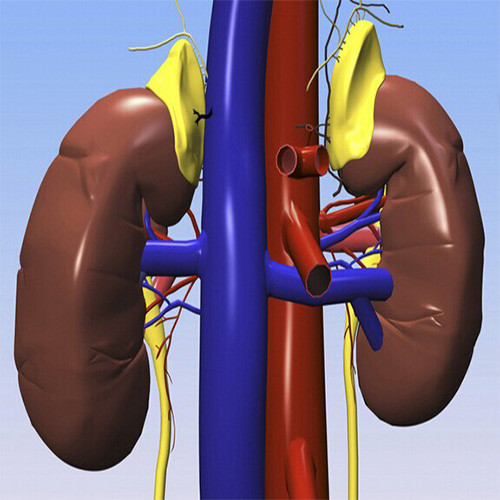

雙腎囊腫

右腎腎囊腫

腎囊腫與正常腎對比

腎囊腫引起腎巨大